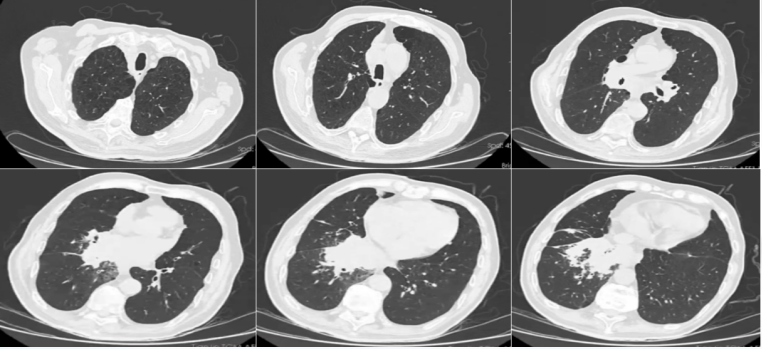

影像学(2024-09-30)

双肺炎症右肺明显,少量胸腔积液肺部占位1

1  患者入院胸部CT